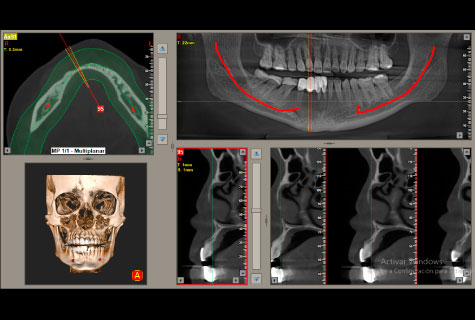

Contamos con un equipo tomográfico dental de los más modernos del país con tecnología de ultima generación para obtener magníficos resultados con una excelente calidad de imagen.

- Único que incluye programa para colocación de implantes virtual.

- Marcación del dentario inferior para un mejor diagnóstico.

Tomografía Cone Beam

- Tomografía de maxilares